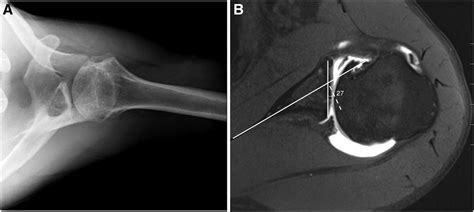

computed tomography image showing glenoid bone loss 781×509

computed tomography image showing glenoid bone loss